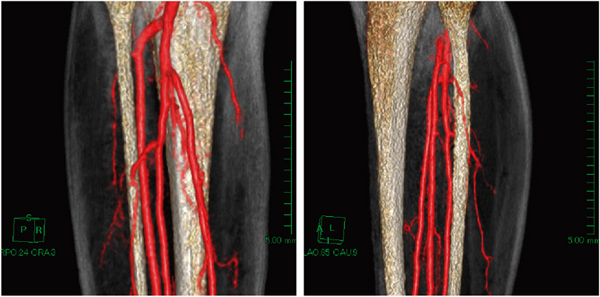

がんや事故,骨髄炎などによって組織欠損を余儀なくされた場合,下腿部の腓骨,筋肉,皮膚を用いて再建術が行われる(血管柄付遊離腓骨皮弁)。この場合の術前シミュレーションとして,下腿部の腓骨とその周辺の筋肉へ向かう腓骨動脈から分岐する末梢動脈の存在(数本分岐することが知られている)および分岐の高さを知ることが,皮弁の栄養血管を把握することにつながり,切除範囲を決める上で大変重要である。

そこで,腓骨動脈から分岐する末梢動脈の描出法として,造影MRAを行った(図5)。MRAは,骨の影響を受けずに血管を描出できることが最大の特長である。しかも,造影MRAは,データ収集方法がCTとは異なるため,動脈血管だけを選択的に描出でき,本症例のような形態を把握するのには大変有用だと考える。しかし,MRAでは骨の情報が乏しいために,骨周辺の血管走行が不明瞭なのが問題点となる。

図5 症例2:下腿部の造影MRAのMIP(maximum intensity projection)像

撮像条件は,3D-T1-TFE法にて下腿部を矢状断像で撮像し,撮像コイルは32ch cardiac torso coilを使用した。Gd造影剤を注入速度3mL/sで注入し,造影後から造影前を差分することで血管を描出する方法を用いた。また,目的血管が筋肉内を走行する穿通枝動脈であるため,循環器内科医の協力のもと,亜硝酸剤スプレーを用いた。高速注入と血管を拡張させていることで,腓骨動脈から分岐する穿通枝動脈が明瞭に描出されている。

骨の形態情報は,T1強調像の骨髄信号が高信号を呈するという事実から,抽出機能を用いて骨(骨髄)のVR像(volume rendering)を作成し(図6),差分画像の動脈のVR像とマルチボリューム表示することで,MRAの弱点である骨との位置関係が明瞭となった(図7,8)。マルチボリューム表示によって,腓骨,筋肉の切除範囲の決定するための臨床的有用性の高い情報が提供できた。